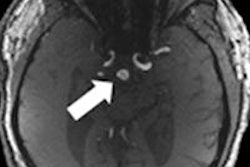

Saudi Arabia now offers intraoperative radiation therapy. Image courtesy of Dr. Yasir Bahadur.

While most of the patients (29) received IORT, only 16 also received external-beam radiotherapy after IORT. Twelve patients developed fat necrosis proved by radiological findings (mammography and/or MRI).